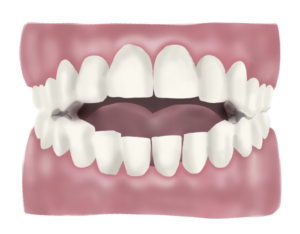

Mossegada oberta

La mossegada oberta la reconeixem perquè les dents de dalt no contacten amb les de baix, això es pot donar a nivell anterior o bé a nivell lateral/posterior de l’arcada dentària.

Perquè és un problema la mossegada oberta?

La mossegada oberta no és una mossegada equilibrada ja que no contacten totes les dents que haurien de contactar i això obliga a una part de les dents a treballar en excés i a l’altre part a no treballar. A part d’això pot generar una sèrie de tensions muscular i lligamentoses a nivell de la mandíbula, articulació temporomandibular i cervicals que portin a estats de dolor, clics o inclús que es transmetin a la resta del cos a través de les cadenes musculars provocant problemes a distància.

Quan un ésser arriba a la consulta amb mossegada oberta el primer que fem és buscar la causa d’aquesta: sempre trobem una llengua que es col·loca entre les dents, tant a l’hora d’empassar saliva, com a l’hora de parlar, com mentre descansem i no la fem servir. En aquest cas la llengua presenta una funció alterada que cal reeducar. Moltes vegades també s’hi suma un hàbit de respiració bucal, que caldrà tractar amb les mateixes premisses que hem explicat a l’apartat anterior, fent un acompanyament per a la reeducació respiratòria.